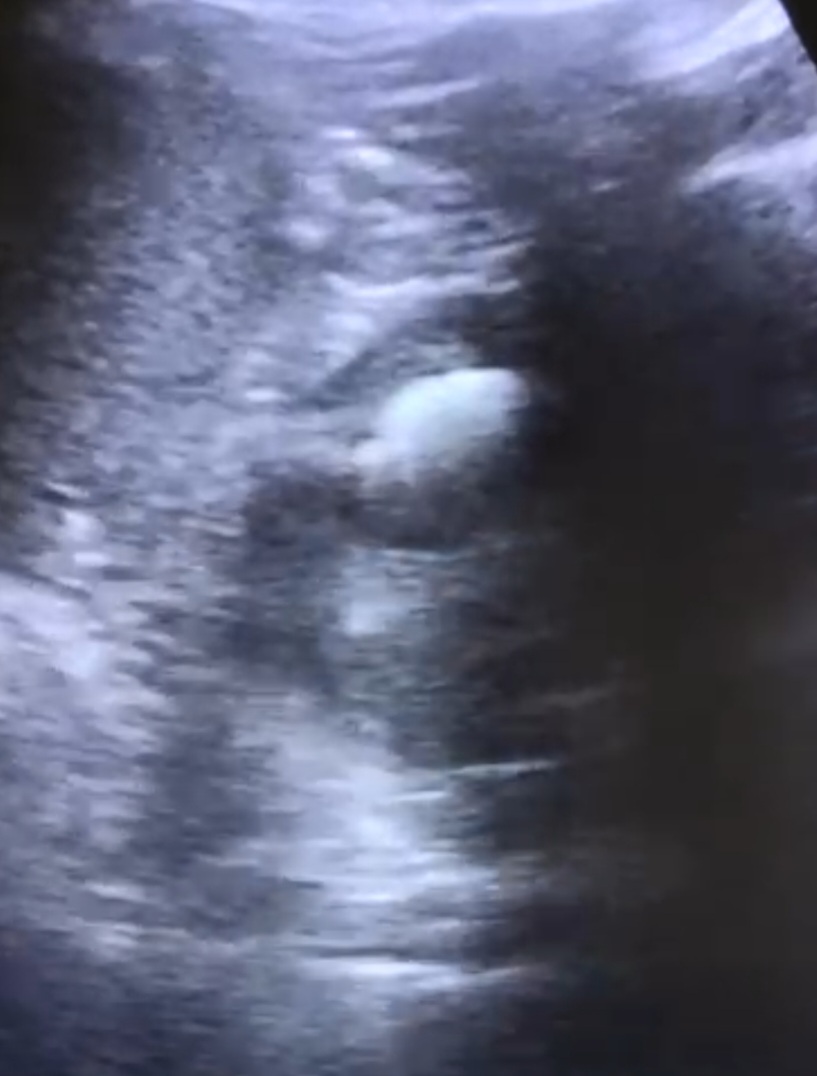

Se deriva a SUH: ID de hernia inguinal no complicada, se cita en consulta externa con cirugía; se realiza ecografía de partes blandas y se descarta la presencia de hernias. Por persistencia de síntomas acude en varias ocasiones a AP; como hallazgos casual test de aliento positivo, se pauta TTX erradicador con posterior negativización. La clínica no cedía, pese a ttx analgésico intercalado, y se acentuó en FID por lo que vuelve a consultar por su MAP y se deriva a SUH con ID de apendicitis/ hernia inguinal/orquitis; con ID de epididimitis se le pauta ATB por 7 días + urocultivo negativo. En AP se solicita cita para urología. Se le vuelve a remitir en otra ocasión desde AP a SUH: ID de dolor abdominal inespecífico y remite a su MAP. ECOABD en su MAP: imagen quística en polo superior renal izquierdo, solicita ECOABD reglada: imagen en la cara lateral del polo superior del riñón izquierdo de características quísticas de 3x2 cm, con imágenes ecogénicas en su interior con sombra acústica y con artefacto en cola de cometa (sugiere naturaleza cálcica).

Se solicita TAC para mejor valoración: Quiste en polo superior del riñón izquierdo, con leche cálcica en interior, que comunica con el sistema excretor.